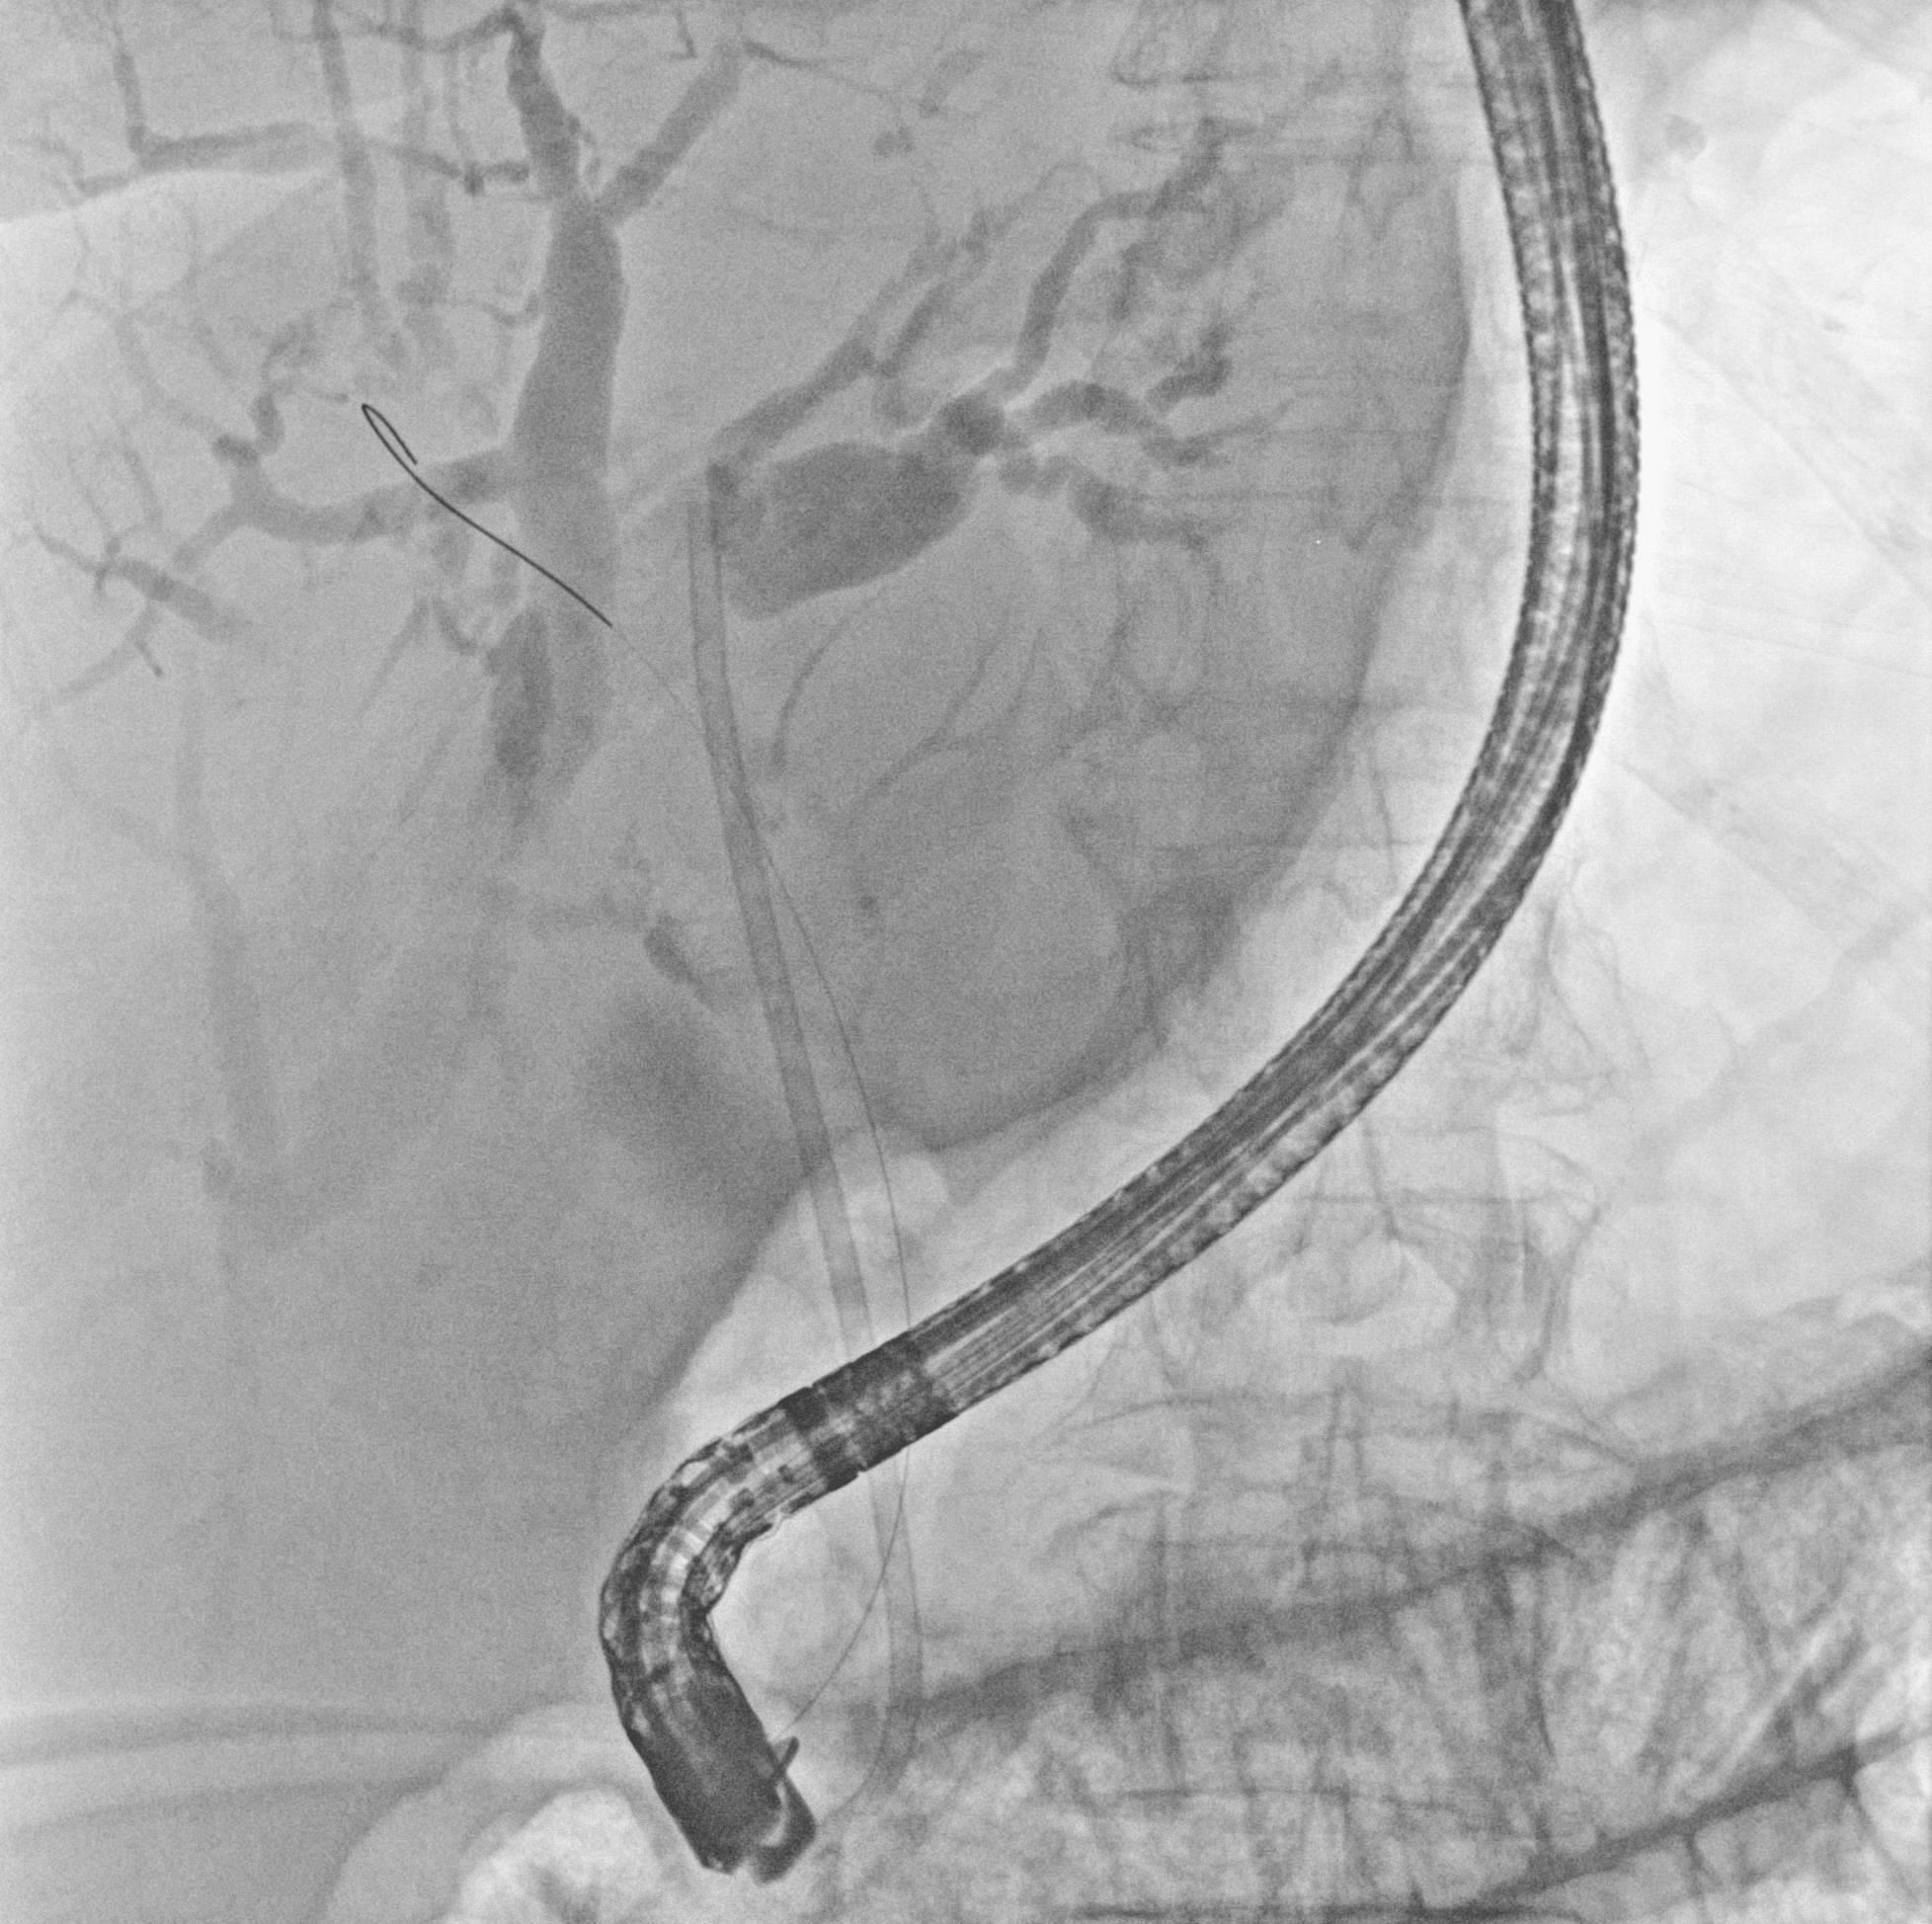

Мобильная рентгеновская С-дуга «Сапфир»

| «Сапфир» — новая мобильная С-дуга производства АО «МТЛ», предназначенная для точной диагностики во время хирургических вмешательств. Режимы работы: рентгеноскопия, рентгенография, цифровая субтракционная ангиография. | Компактная конструкция и удобное управление делают систему универсальным инструментом для операционных различного профиля, позволяя проводить как рутинные, так и специализированные процедуры. Подходит для широкого спектра исследований и хирургических вмешательств под рентгеновским контролем, включая травматологию, ортопедию, урологию, общую хирургию и обследование периферических сосудов. |

Высокое качество визуализации